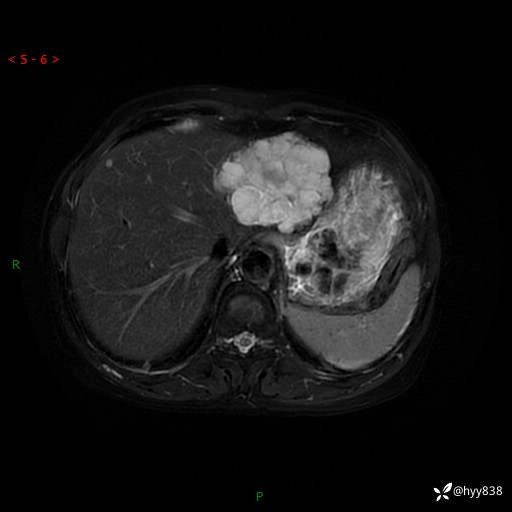

肝脏MRI平扫(同反相位)

T2WIfs+DWI

增强(动脉期+静脉期+延迟期)